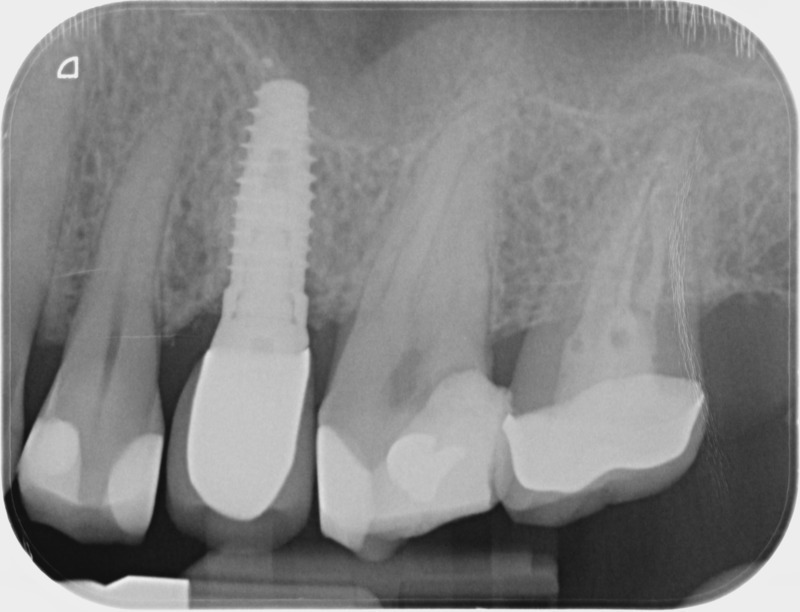

Après

• Reprise de traitement endodontique : La manœuvre consiste à retourner à l’intérieur des racines d’une dent déjà traitée. Il arrive occasionnellement qu’une nouvelle inflammation se déclare suite à une reprise de carie ou une fracture de la dent, ou si le premier traitement endodontique est incomplet. Après s’être assuré que la dent lésée était conservable, il convient de désinfecter de nouveau le réseau canalaire parfois très complexe. La nouvelle obturation des canaux devra être protégée aussi rapidement que possible pour éviter une éventuelle contamination bactérienne.